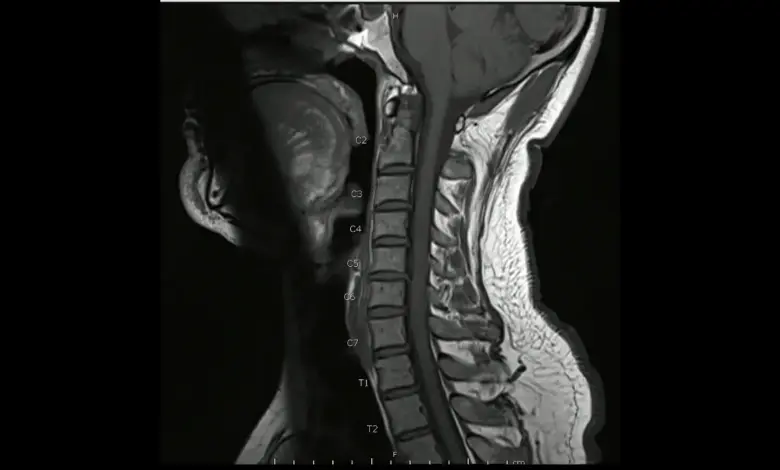

A coluna cervical tem sete vértebras e curvatura fisiológica que protege a medula e permite mobilidade.

Quando há aumento ou inversão dessa curva, surgem quadros como hiperlordose, hipercifose e síndrome da cabeça caída.

O diagnóstico combina exame físico, radiografias em ortostatismo, tomografia, ressonância magnética e, quando indicado, testes eletrofisiológicos.